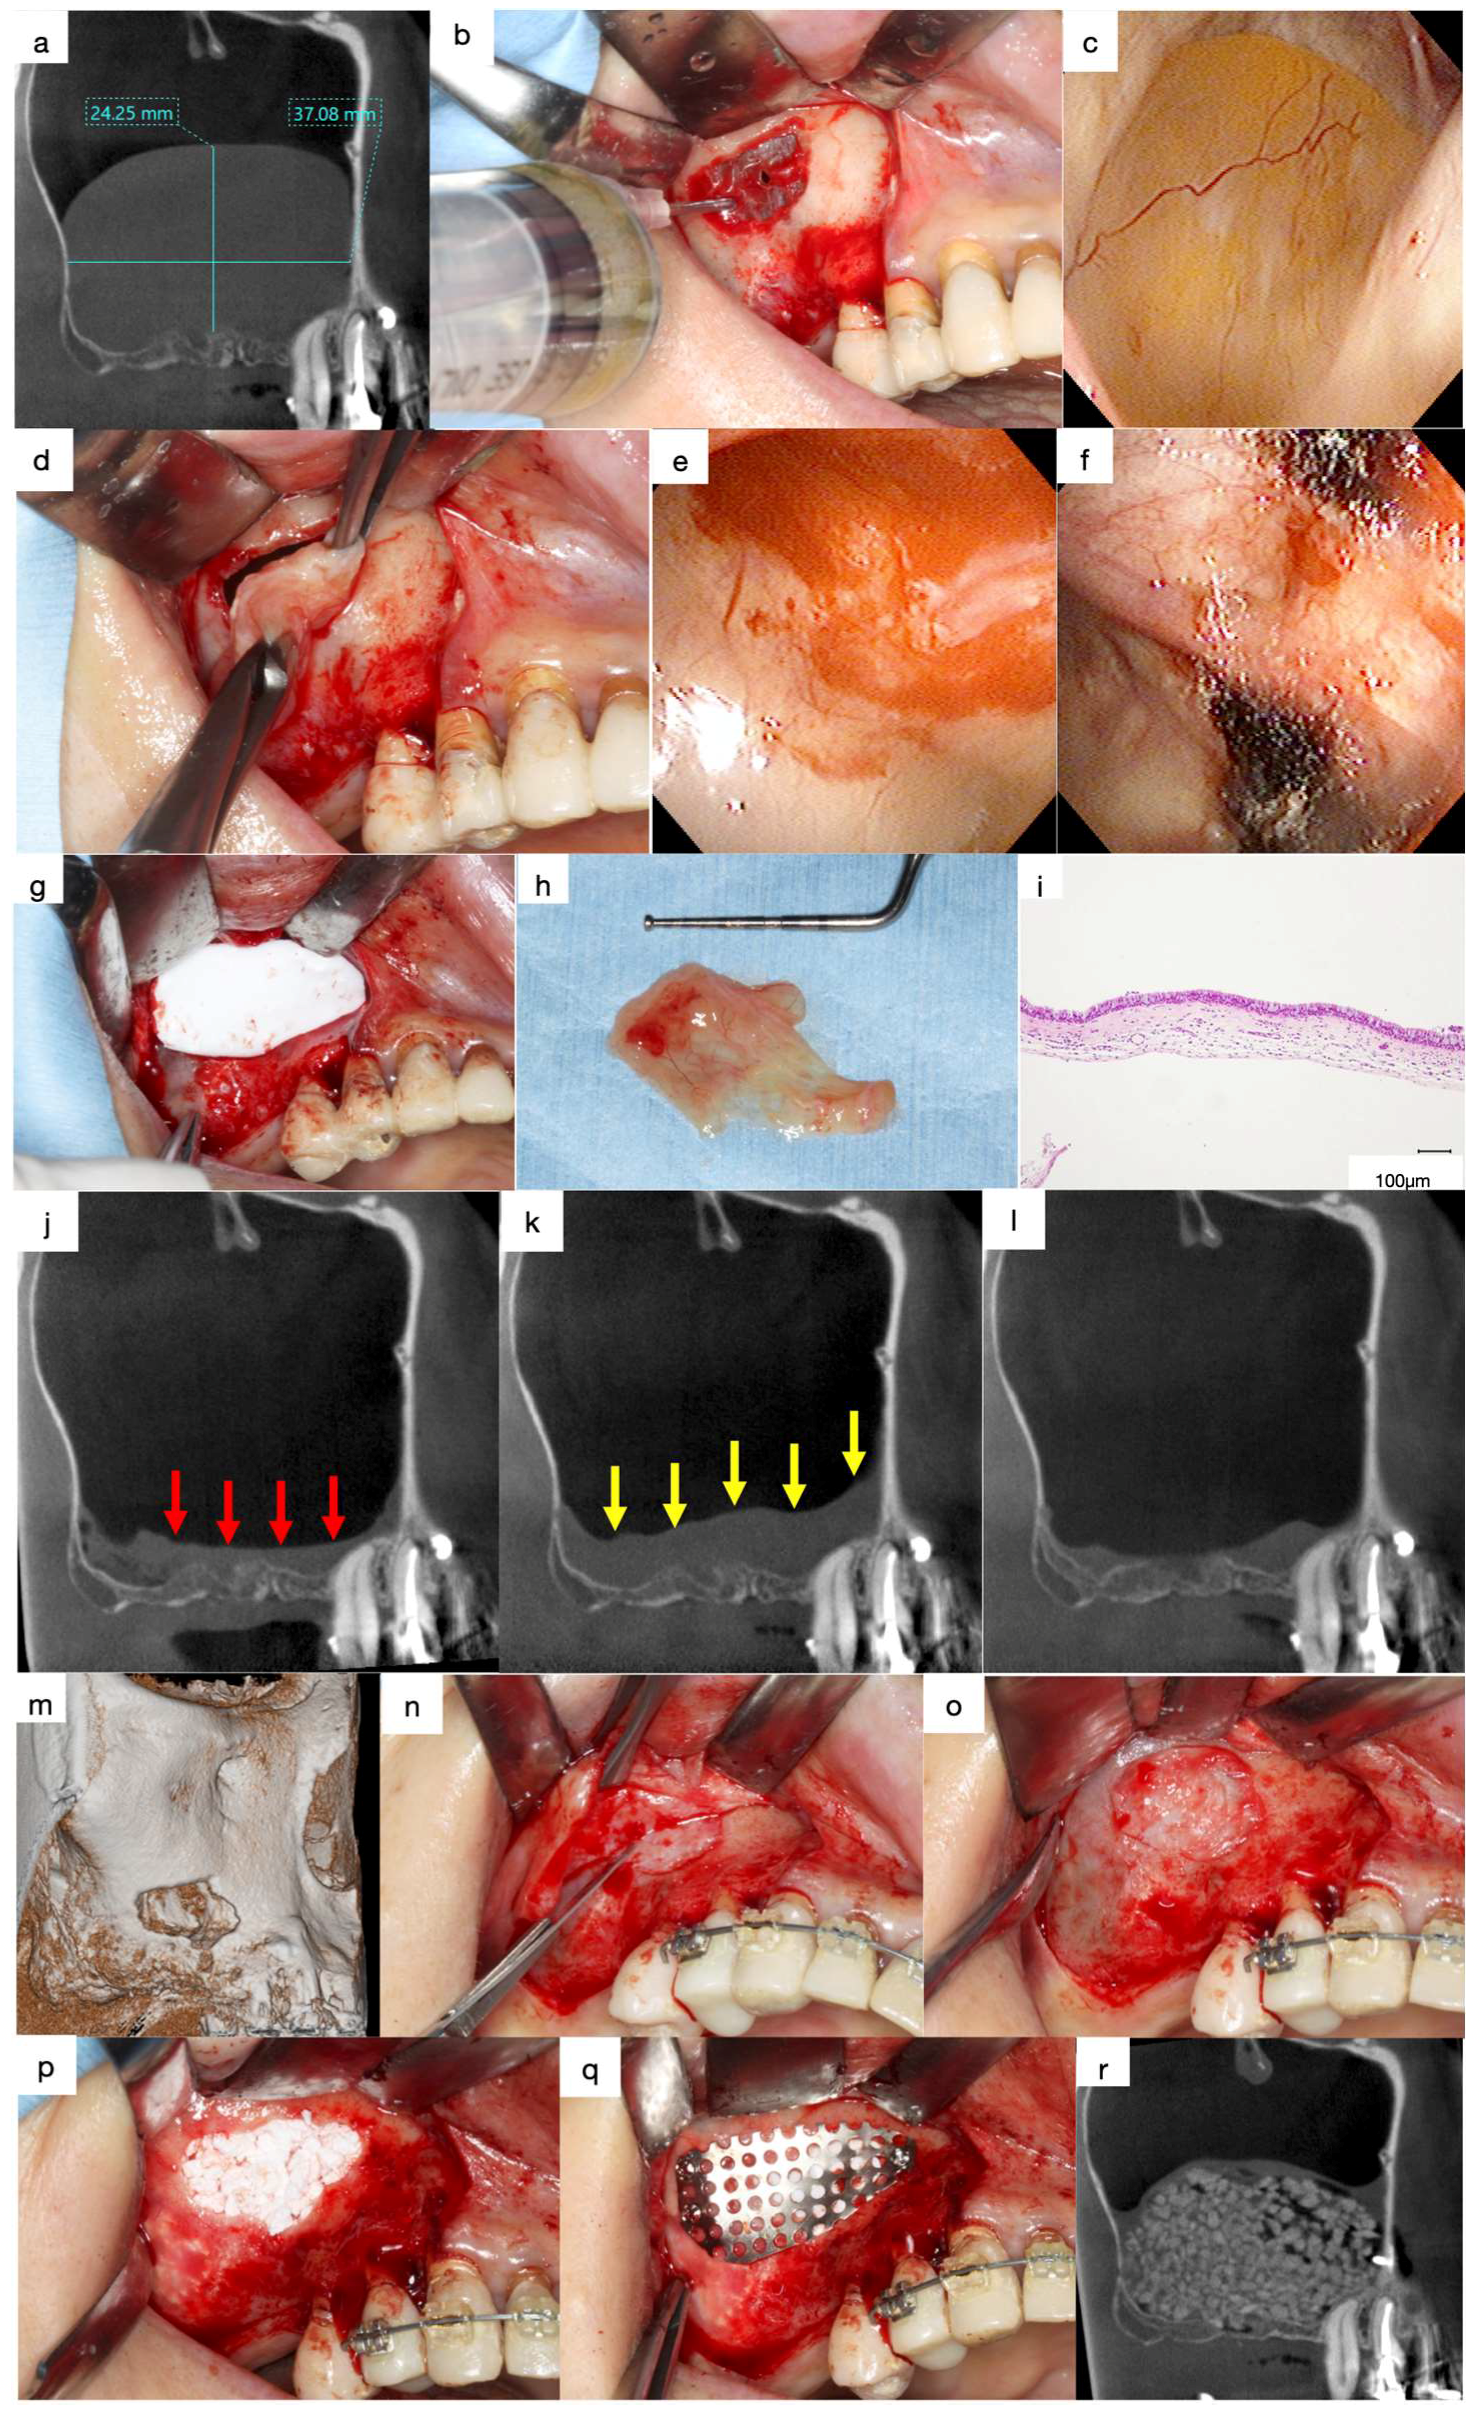

A 69-year-old male was referred to our clinic in 2016 with chief complaints of headache, nasal congestion, and postnasal discharge. He had undergone implant treatment with sinus floor elevation using Bio-Oss 10 years prior. The implants replacing 17 and 16 had been shed two months before the first visit, and the patient had developed sinusitis.

The mediodistal section of the CT image acquired at the first visit revealed prominent swelling of the sinus membrane. Pneumatic space was not observed in the maxillary sinus (Figure 9a). Radiolucent areas containing radiopaque particles were observed in the regions surrounding 17 and 16. Furthermore, artificial bone was absent at the floor of the maxillary sinus in the region surrounding 16, suggesting that the maxillary sinus was interconnected with the socket of the lost implant (Figure 9a, red arrows).

Figure 9.

(a) Mediodistal section of the CT image acquired at the first visit. Prominent swelling of the sinus membrane can be observed, and no pneumatic space is present in the maxillary sinus. Artificial bone is absent at the floor of the maxillary sinus near 16 (red arrow). (b) The soft tissues surrounding 17 and 16 were removed. (c) Artificial bone granules were observed in the removed soft tissues. (d) Radiograph of the removed soft tissues surrounding 17. Radiopaque particles of various sizes were observed in the soft tissue. (e) Radiopaque particles of various sizes can be observed in the soft tissue surrounding 16. (f) Histological decalcified specimen of the soft tissue surrounding 17 (haematoxylin and eosin staining). Bio-Oss granules can be observed among the fibrous connective tissues with moderate infiltration of inflammatory cells, and only small bone tissues remain beside the Bio-Oss granules (yellow arrows). (g) Severe infiltration of inflammatory cells was observed in the fibrous connective tissue surrounding 16, and no live bone remains around the Bio-Oss granules. (h) Bone biopsy performed on the lateral wall. (i) White particles are grossly embedded in the harvested hard tissue. (j) Radiograph of the specimen showing dense radiopaque particles in the harvested tissue. (k) The demineralised histological specimen (H.E. staining) shows that newly formed live bone is present adjacent to the Bio-Oss granules, and many foreign body giant cells can be observed around the Bio-Oss granules.

The removal of the soft tissue surrounding 17 and 16 revealed artificial bone granules (Figure 9b,c). Radiographs acquired subsequently revealed radiopaque particles of varying sizes within the tissues (Figure 9d,e). The demineralised histological specimen (H&E staining) revealed the presence of Bio-Oss granules in the fibrous connective tissues (Figure 9f,g). Moderate infiltration of inflammatory cells was observed in the fibrous connective tissues in the regions surrounding 17, and only small bone tissues were observed beside the Bio-Oss granules (Figure 9f, yellow arrows). In contrast, severe infiltration of inflammatory cells was observed in the regions surrounding 16, and no live bone was observed around the Bio-Oss granules (Figure 9g). These findings suggest that peri-implantitis disrupted osseointegration and that Bio-Oss granules were isolated from the newly formed bone tissue. Furthermore, the infection spread to the maxillary sinus through the Bio-Oss granules in the regions surrounding 16, leading to sinusitis.

A bone biopsy was performed on the lateral wall after receiving consent from the patient (Figure 9h,i). Radiographs of the harvested specimen revealed dense radiopaque particles (Figure 9j). The demineralised histological specimen (H&E staining) revealed the presence of newly formed live bone adjacent to the Bio-Oss granules (Figure 9k). Furthermore, numerous foreign body giant cells were observed around the Bio-Oss granules, suggesting that the biological reaction to the Bio-Oss granules had persisted for 10 years postoperatively. Thus, non-absorbable bone materials are associated with a risk of inducing sinusitis in patients with peri-implantitis when used as bone material for sinus floor elevation.